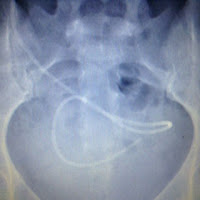

| Abdomen view of current distal catheter and old catheter (far left) |

| Close up of distal catheter (end) |

Right frontal ventriculo-peritoneal shunt is seen coursing through the right neck soft tissues, anteriorly through the chest wall, and coiling in the pelvis. Catheter fragments in the right neck soft tissues and right abdominal wall likely represent retained shunt fragments. No evidence of fracture or kink.

VP shunt catheter, as described, without evidence of fracture or

kink.